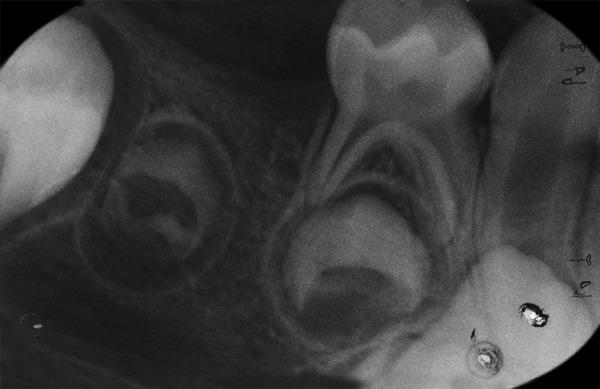

Hidden caries is a dentinal lesion beneath the dentinoenamel junction, visible on radiographs. A single report described this lesion in primary dentition. This case report describes a case of hidden caries in a mandibular second primary molar, misdiagnosed as malignant swelling. A 3-year-old white girl was referred to the Department of Pediatric Dentistry with a chief complaint of pain and extraoral swelling on the right side of the mandible for the last 3 months. She was earlier referred to the surgical department for biopsy of the lesion. Radiographic and computed tomography scan examination showed a periapical lesion with buccal plate resorption and radiolucency beneath the enamel on the mesial part of tooth 85. The tooth was extracted, and follow-up of 2 years showed normal development of tooth 45. The main problem is early detection and treatment, since the outer surface of enamel may appear intact on tactile examination.

隐匿性龋是位于牙本质釉质界下方的牙本质病变,在X线片上可见。有一份报告描述了乳牙列中的这种病变。本病例报告描述了一例下颌第二乳磨牙隐匿性龋被误诊为恶性肿胀的病例。一名3岁白人女孩因右侧下颌疼痛和口外肿胀3个月为主诉被转诊至儿童牙科。她之前被转诊至外科进行病变活检。X线片和计算机断层扫描检查显示85号牙近中部分根尖周病变伴颊侧板吸收以及釉质下方的透射区。该牙被拔除,2年的随访显示45号牙发育正常。主要问题是早期发现和治疗,因为在触诊检查时釉质外表面可能看起来完好无损。